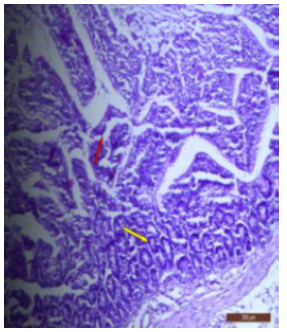

The ileal mucosa of control rat was built up of numerous folds forming the villi, through which connective tissue of the lamina propria containing tubular glands i.e., crypts of Leiberkühn were present (Figure 18). The epithelial lining of the villi was composed of Paneth cells and intestinal glands (Figure 19). In fluorotic rats, there were abnormal shaped, damaged and broken villi with bulbous tips. Lymphatic dilation and haemorrhaged in lamina propria were also seen (Figure 20). In the ileal mucosa, prominent inflammation, distortion of crypts with shredded cells inside the crypts were visible (Figure 21). Swollen and necrotic crypts were present (Figure 22). The ileal tissue showed disruptions in the normal mucosal architecture with signs of villous atrophy and cell infiltration (Figure 23). Lymphatic infiltration was prominent and numerous enlarged lymph nodules appeared in lamina propria of villi. There were ill-defined cell boundaries, vacuolated cytoplasm and pyknotic nuclei (Figure 24).

Figure 20: T.S. of ileum of rat treated with 600 mg NaF/kg b.w./day for 40 days showing broken villous and necrotic crypts (↑).H&E × 100.

Figure 21: T.S. of ileum of rat treated with 600 mg NaF/kg b.w./day for 40 days showing inflammation (↑) in the mucosa. H&E × 100.

Figure 22: T.S. of ileum of rat treated with 600 mg NaF/kg b.w./day for 40 days showing swollen (↑), broken villus and necrotic tips (↑). H&E × 100.

Figure 23: T.S. of ileum of rat treated with 600 mg NaF/kg b.w./day for 40 days showing disrupted mucosal structure. H&E × 40.

Figure 24: T.S. of ileum of rat treated with 600 mg NaF/kg b.w./day for 40 days showing abnormalities in the lymph nodes (↑). H&E × 100.